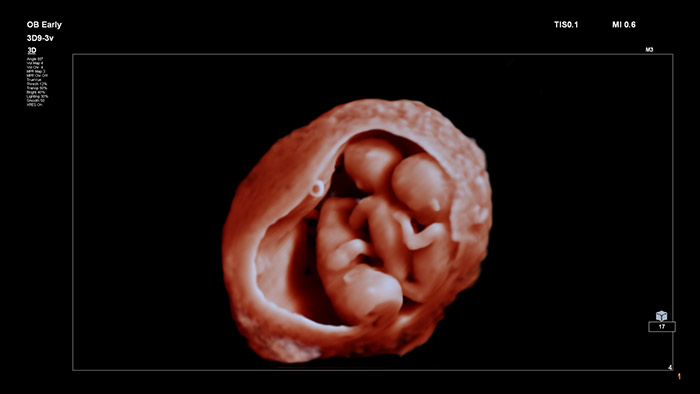

TrueVue

Imagerie réaliste :

Grâce à des images innovantes et extrêmement détaillées ainsi qu’à la possibilité de manipuler une source de lumière virtuelle flexible, TrueVue offre aux cliniciens et aux futures mères des images incroyablement réalistes du fœtus pendant la grossesse.